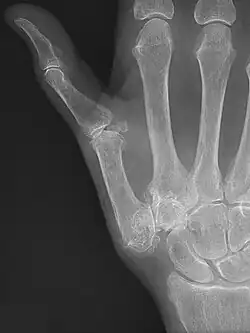

Diagnosis

TMC OA is diagnosed based on symptoms and signs.[8] Radiographs can confirm the diagnosis and the severity of TMC OA. Other diagnoses in this region include scaphotrapezial trapezoid arthritis and first dorsal compartment tendinopathy (De Quervain syndrome) although these are usually easy to distinguish.